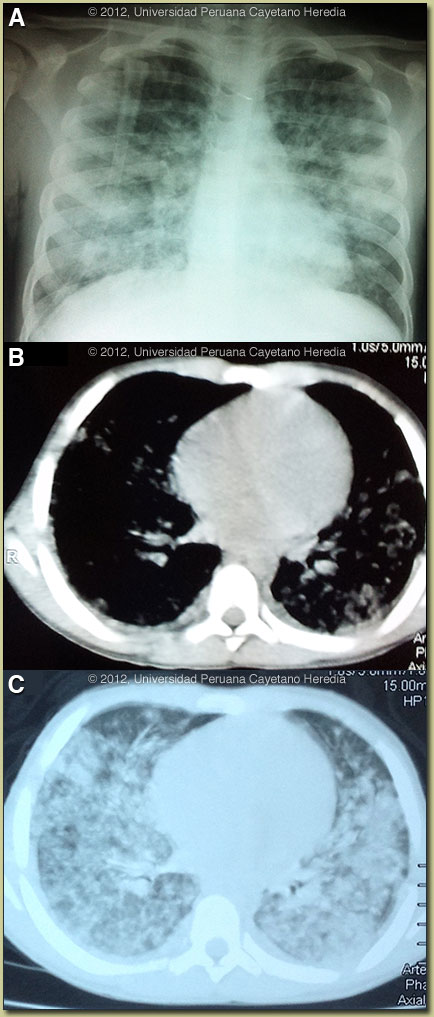

![]() ![]() History: 10-year-old previously very healthy male presents with a 4-day history of fever and a rash starting on the trunk and spreading to involve the entire body. One day prior to admission he developed dyspnea and was brought to the hospital. There was no cough or sputum production. No arthralgia or myalgia. Epidemiology: Lifelong resident of the city of Iquitos with no recent travel to rural jungle areas. Fully vaccinated according to the Peruvian guidelines, including yellow fever and hepatitis B. Mother is alive and well. No known TB exposure. Physical Examination: BP 90/60, HR 130, RR 38, Temp 38.5°C. Well developed, well nourished. Ill-looking with obvious respiratory distress. No icterus, sclerae normal. Chest: bilateral crackles. Abdomen: soft, normal bowel sounds, no hepatosplenomegaly. Skin: diffuse rash over entire body (Images to be provided on Diagnosis and Discussion page). Mucosa: no lesions noted but complaining of some oral discomfort. Neurologic examination normal. Laboratory Results: Hb: 8.9; WBC 10,400 (no differential done); Platelets 780,000; ALT 8; AST 10. Normal renal function. O2 saturation 94%. Chest X-ray shown in Image A, and Chest CT in Images B, C. |

Diagnosis: Acute Varicella infection complicated by pneumonitis.

![]() ![]() Discussion: Acute Varicella Zoster Virus (VZV) infection is a clinical diagnosis with a characteristic vesicular rash [see Images D-G, taken on Day 10 of illness] of the superficial dermis involving the trunk, face, and often oropharynx. Children, as opposed to adults, often have scalp lesions. Notably, several crops of fresh vesicles may erupt every few days, becoming crusted and lasting for a total of 6-10 days. The rash usually begins centrally and spreads outwards and may involve the palms and soles, as in this case. In non-compromised hosts new lesions should not occur beyond the first week of illness, which was the case here. In contrast, the lesions of smallpox begin on the extremities with all lesions occurring at the same time and appearing and evolving in a similar manner. The incubation period of varicella is 10-21 days, most commonly about 14 days. There is currently an outbreak in Iquitos and our patient had been exposed to several other neighborhood children with varicella. More severe disease with complications have been reported in outbreak settings. Varicella vaccination is not practiced in any developing country. In countries with highly vaccinated populations, severe cases in children are now rare and usually restricted to compromised hosts especially those with hematologic malignancies. Complications of varicella are much more common in adults, especially varicella pneumonia, which occurs in up to 20% of adult cases in certain settings. Pneumonia when it occurs usually develops in the first week of rash onset. However, even healthy children under the age of 12 can occasionally develop cerebellitis, pneumonia, purpura, hepatitis, and soft tissue infections. Secondary bacterial infections can be severe, particularly if they are associated with group A streptococcus [see Gorgas Case 2008-09]. Our 10-year-old patient has no history or physical findings compatible with immunocompromise and HIV should have manifest by this age; nevertheless no specific workup was available or done during his hospitalization. CT findings of varicella pneumonia [AJR Am J Roentgenol. 1999 Jan;172(1):113-6; AJR Am J Roentgenol. 2007 Jun;188(6):W557-9; and N Engl J Med. 2010 Apr 1;362(13):1227] include interstitial inflammation, well-defined and ill-defined nodules, nodules with surrounding ground glass attenuation, patchy ground glass attenuation, and coalescence of nodules. Areas with many coalescent nodules in close proximity may appear as areas of consolidation. These radiologic features disappear rapidly in concert with the healing of the corresponding skin lesions in normal hosts. In the tropics, including in developing countries, the age distribution of acute varicella differs markedly from that in temperate climates. Only the minority of individuals acquires varicella in childhood, so that more than 50% of adults in their twenties remain non-immune and clinical varicella in adults is common. In temperate climates only 2% of varicella cases occur in those over twenty years of age. In the US and Europe, varicella outbreaks in immigrant and refugee communities are increasingly frequent events. The reasons for the altered behavior of VZV virus in the tropics have not been elucidated. The patient fatigued rapidly after admission and was admitted to the ICU for mechanical ventilation. The benefit of acyclovir in typical uncomplicated acute varicella in children under the age of 12 is modest at best and is not routinely recommended in authoritative guidelines. In this severe case the patient was treated with IV acyclovir as well as broad-spectrum antibiotics in case of superinfection obscured by the extensive viral pneumonitis. The use of steroids in varicella pneumonia is not well studied and is of unproven benefit. He improved rapidly and was extubated on the 3rd hospital day with marked improvement of the chest X-ray [Image H] and resolution of much of the nodular disease as expected. Acknowledgements: We thank Dr. Nicolás Barrós Baertl, as well as Gorgas Course Pediatrician Professors Manuel Gutierrez and Eduardo Verne for helpful discussions.